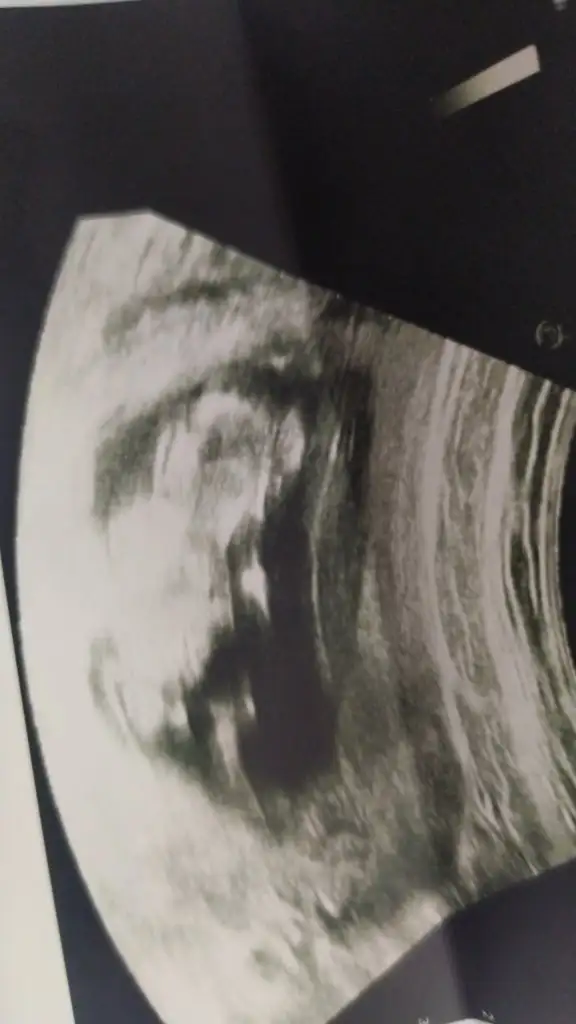

Dikkatli bakar mısınız lütfen sanki bir çıkıntı var gibi pipiye benziyorKız görünüyor kaç haftalık USG 11 12 13 haftalar olmalı![]()

Evet baktım acısı paralel olarak iniyorDikkatli bakar mısınız lütfen sanki bir çıkıntı var gibi pipiye benziyor

Yani ne demek oluyor pekiEvet baktım acısı paralel olarak iniyor![]()

Kız görünüyorYani ne demek oluyor peki

Erkek görünüyorbenim usg leri de yorumlayabilir misiniz acaba![]()

Peki kesin midir değişir mi sonradan bu hafta eşime sürpriz yapmayı düşünüyorumdaKız görünüyor![]()

Tahminim kız ama yinede Dr bekleyinPeki kesin midir değişir mi sonradan bu hafta eşime sürpriz yapmayı düşünüyorumda